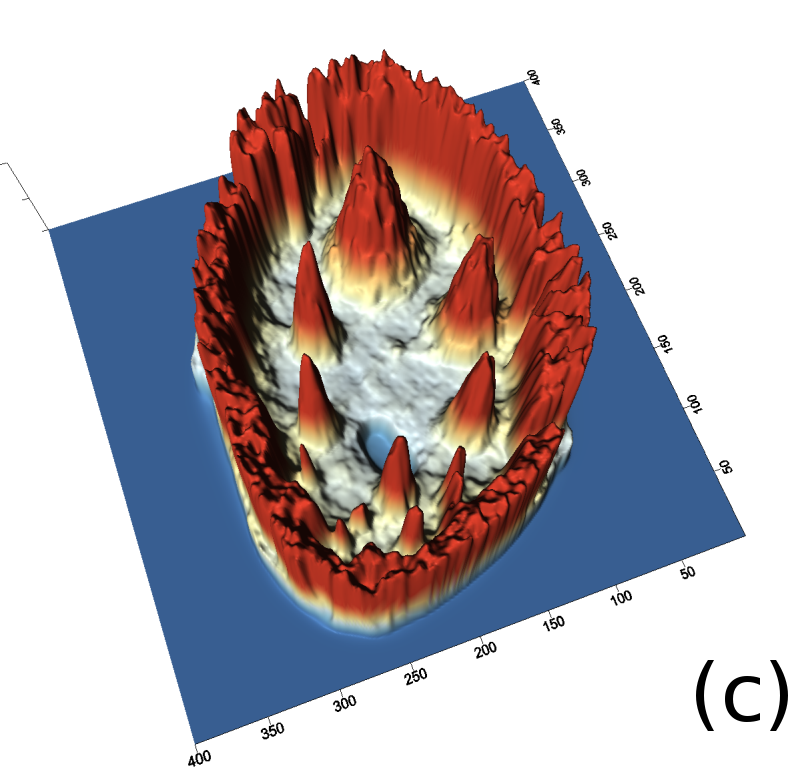

Reconstructed images are presented in Fig. 4. Since CGLS-TV- reconstruction might look more appealing than CGLS-EL we also show the surface representations of reconstructed images (see Fig. 5) and horizontal middle cross-sections (see Fig. 6).

One can notice that CGLS reconstruction is very noisy. CGLS-TV method better suppresses noise, however smooth features are strongly affected by the “staircasing” effect. CGLS-TV- method provides reconstruction with smoother features and CGLS-EL method resolves smooth features even better (e.g. cone-shaped parabola). Although CGLS-EL method performs very well for smooth objects one can notice the wave-like variations of intensity in the background and also at the top of the rectangle (see Fig. 6). This issue can be explained by the properties of our regularizer, in contrast to TV, our penalty does not seek the sparsest solution and does not penalize strongly (pushing to the constant value) a small intensity perturbations. The EL term tends to preserve all sharp edges while uniform noise is smoothed isotropically with the Laplacian. In Fig. 6 one can see that the CGLS-EL method provides better recovery of smooth features while slightly higher (compare to TV and TV-) perturbations visible in uniform areas (the top of the rectangle), however, the edges of the rectangle are defined sharper with the EL penalty.